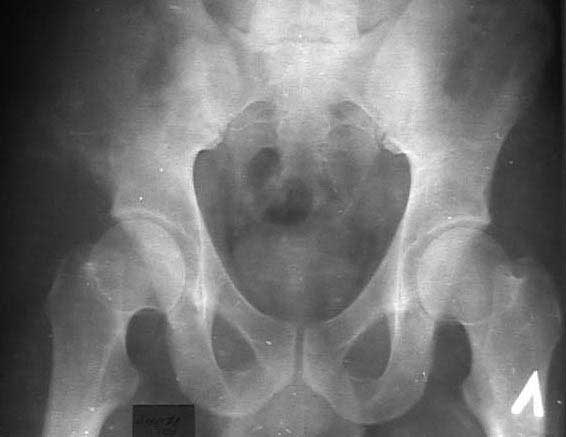

В 2002 году буквально "промелькнул" и исчез пациент с подобным остеолизом. Обследован (биопсия ) в отделении костной онкологии, а затем у дерматологов. Причиной остеолиза признан актиномикоз. К сожалению в то время не удалось выполнить КТ, а рентгенограммы не качественные - в приложении.

Имя     : 01.02.02..jpg

Тип     : image/jpg

Размер  : 21695 байтов

Url     : http://weborto.net:8080/pipermail/ortho/attachments/20110406/5444d703/attachment-0004.jpg